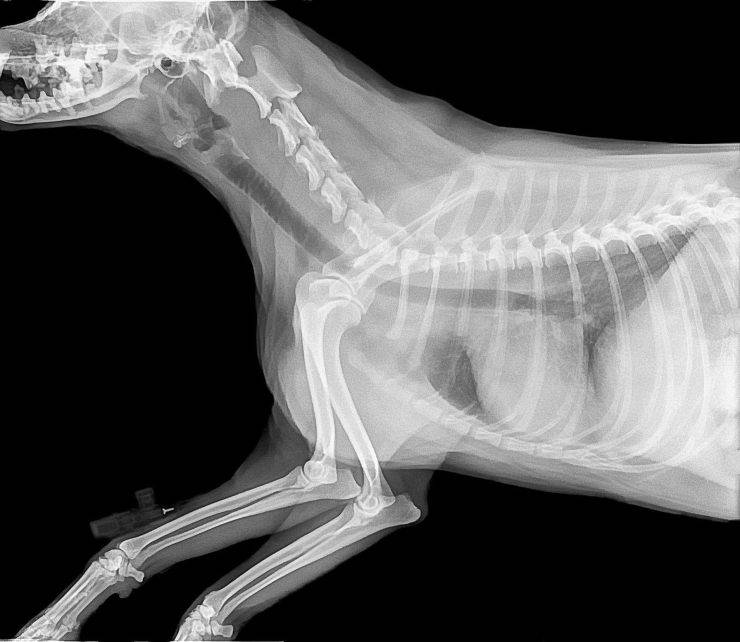

Además, esta posición de las piernas provoca dolor en las articulaciones y mediante el uso de rayos X se observará cómo los huesos no se adaptan bien entre sí y adquieren posiciones extrañas. Según la gravedad de la situación, también pueden tener un tórax plano, que se ha deformado al dejar el peso del perro en contacto constante con el suelo, provocando problemas respiratorios.